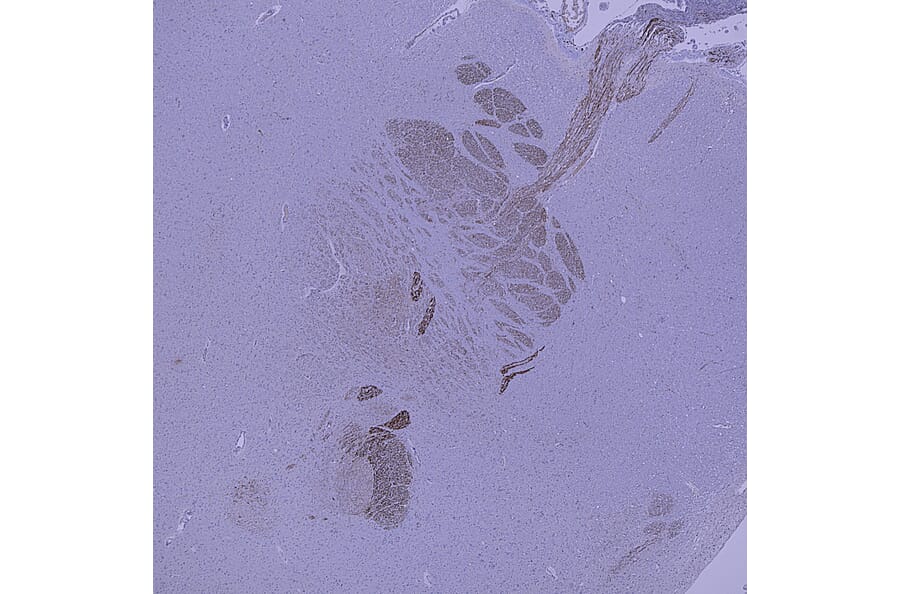

Immunohistochemistry analysis of a NBF fixed paraffin embedded human midbrain section with Anti-Peripherin Antibody (A85430) at a dilution of 1:2,000 detected with DAB (brown) using the Vector Labs ImmPRESS method and reagents with citra buffer retrieval. Counterstained with Hematoxylin (blue). Anti-Peripherin Antibody (A85430) strongly labels the cytoplasm of neuronal peripheral projections. Note: this antibody performs well in testing with 4% PFA and standard NBF fixed mouse, rat and human tissue.